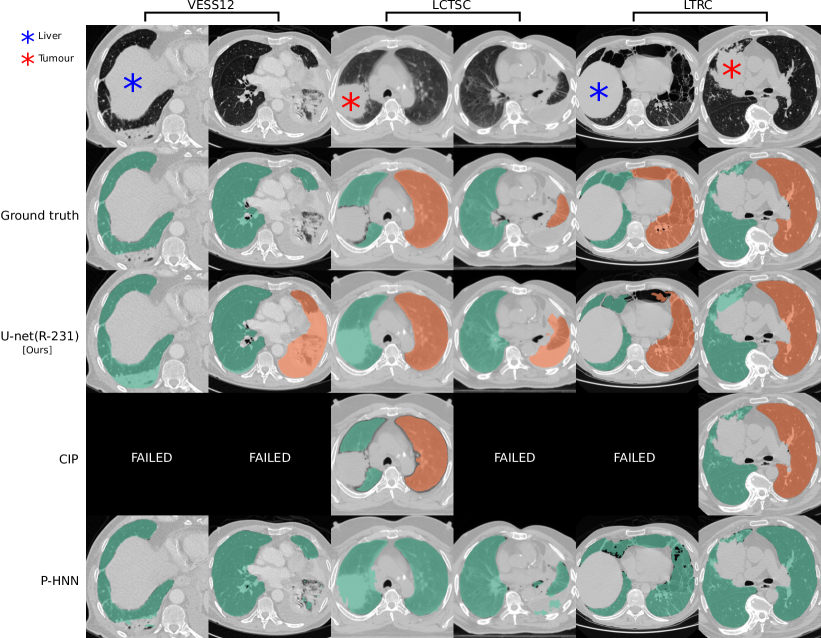

Refer to caption

Figure 3: Ground truth annotations in public datasets lack coverage of pathologic areas: Segmentation results for cases in public datasets where the masks generated by our U-net(R-231) yielded low Dice similarity coefficients when compared to the ground truth. Note that public datasets often do not include high-density areas in the segmentations. Tumours in the lung area should be included in the segmentation while the liver should not.

Models trained on routine data achieve improved evaluation scores compared to models trained on publicly available study data. U-net, ResU-net, and Deeplab v3+ models, when trained on routine data (R-36), yielded the best evaluation scores on the merged test dataset (All, n = 62). The U-net yields mean DSC, HD95, and MSD scores of 0.96 ±plus-or-minus\pm 0.08, 9.19 ±plus-or-minus\pm 18.15, 1.43 ±plus-or-minus\pm 2.26 when trained on R-36 [U-net(R-36)] and 0.92 ±plus-or-minus\pm 0.14, 13.04 ±plus-or-minus\pm 19.04, 2.05 ±plus-or-minus\pm 3.08 when trained on VISC-36 (R-36 versus VISC-36, p = 0.001, 0.046, 0.007) or 0.94 ±plus-or-minus\pm 0.13, 11.09 ±plus-or-minus\pm 22.9, 2.24 ±plus-or-minus\pm 5.99 when trained on LTRC-36 (R-36 versus LTRC-36, p = 0.024, 0.174, 0.112). This advantage of routine data for training is also reflected in results using other combinations of model architecture and training data. Table III lists the evaluation results in detail. We determined that the influence of model architecture is marginal compared to the influence of training data. Specifically, the mean DSC does not vary for more than 0.02 when the same combination of training and test set was used for different architectures (Table III). Compared to readily available trained P-HNN model, the U-net trained on the R-231 routine dataset [U-net(R-231)] yielded mean DSC, HD95, and MSD scores of 0.98 ±plus-or-minus\pm 0.03, 3.14 ±plus-or-minus\pm 7.4, 0.62 ±plus-or-minus\pm 0.93 versus 0.94 ±plus-or-minus\pm 0.12, 16.8 ±plus-or-minus\pm 36.57, 2.59 ±plus-or-minus\pm 5.96 (p = 0.024, 0.004, 0.011) merged test dataset (All, n = 62). For comparison with the CIP-algorithm, only volumes for which the algorithm did not fail were considered. On the merged dataset (All, N=62) the algorithms yielded mean DSC, HD95, and MSD scores of 0.98 ±plus-or-minus\pm 0.01 ,1.44 ±plus-or-minus\pm 1.09 ,0.35 ±plus-or-minus\pm 0.19 for the U-net(R213) compared to 0.96 ±plus-or-minus\pm 0.05, 4.65 ±plus-or-minus\pm 6.45, 0.91 ±plus-or-minus\pm 1.09 for CIP (p = 0.001, <<0.001, <<0.001). Detailed results are given in Table IV. Fig. 2 shows qualitative results for cases from the routine test sets and Fig. 3 shows cases for which the masks generated by the U-net(R-231) model yielded low DSCs when compared to the ground truth. We created segmentations for the 55 cases of the LOLA11 challenge with the U-net(R-231) model. The unaltered masks yielded a mean overlap score of 0.968 and with dense areas removed 0.977. Table V and Fig. 4 show results for tumour overlap on the 318 volumes of the Lung1 dataset. U-net(R-231) covered more tumour volume mean/median compared to P-HNN (60%/69% versus 50%/44%, p << 0.001) and CIP (34%/13%). Qualitative results for tumour cases for U-net(R-231) and P-HNN are show in Figs. 5b, c. We found that 23 cases of the Lung1 dataset had corrupted ground-truth annotation of the tumours (Fig. 5d). Fig. 5e shows cases with little or no tumour overlap achieved by U-net(R-231).

We showed that training data, sampled from the clinical routine, improves generalizability to a wide spectrum of pathologies compared to public datasets. We assume this lies in the fact that many publicly available datasets do not include dense pathologies such as severe fibrosis, tumour, or effusions as part of the lung segmentation. Further, they are often provided without guarantees about segmentation quality and consistency. While the Anatomy3 dataset underwent a thorough quality assessment, the organisers of the VESSEL12 dataset merely provided lung segmentations as a courtesy supplement for the task of vessel segmentation, and within the LCTSC dataset, “tumour is excluded in most data” and “collapsed lung may be excluded in some scans” [5]. Results indicate that that both, size and diversity of the training data, are relevant. State-of-the-art results can be achieved with images from only 36 patients which is in line with previous works [41] achieving a mean DSC of 0.99 on LTRC test data using the U-net(R-36) model. A large number of segmentation methods are proposed every year, often based on architectural modifications [31] of established models. Isensee et al. [31] showed that such modified design concepts do not improve, and occasionally even worsen, the performance of a well-designed baseline. They achieved state-of-the-art performance on multiple, publicly available segmentation challenges relying only on U-nets. This corresponds to our finding that architectural choice had a subordinate effect on performance. At the time of submission, the U-net(R-231) achieved the second highest score among all competitors in the LOLA11 challenge. In comparison, the first ranked method [22] achieved a score of 0.980 and a human reference segmentation achieved 0.984 [41]. Correspondingly, the U-net(R-231) model achieved improved evaluation measures (DSC, HD95, MSD and tumour overlap) compared to two public algorithms. There are limitations of our study that should be taken into account. Routine clinical data vary between sites. Thus, extraction of a diverse training dataset from clinical routine may only be an option for centres that are exposed to a wide range of patient variety. Evaluation results based on public datasets are not fully comparable. For example, the models trained on routine data compared to other datasets yielded lower performance in terms of DSC on the LCTSC test data. However, the lower scores for models trained on routine data in LCTSC can be attributed to the lack of very-dense pathologies in the ground truth masks. Fig. 3 illustrates cases for which the R-231 model yielded low DSC. The inclusion or exclusion of pathologies such as effusions into lung segmentations is a matter of definition and application. While pleural effusions (and pneumothorax) are technically outside the lung, they are assessed as part of lung assessment, and have a substantial impact on lung parenchyma appearance through compression artefacts. Neglecting such abnormalities would hamper automated lung assessment, as they are closely linked to lung function. In addition, lung masks that include pleural effusions greatly alleviate the task of effusion detection and quantification, thus making it possible to remove effusions from the lung segmentation as a post-processing step. We proposed a general lung segmentation algorithm relevant for automated tasks in which the diagnosis is not known beforehand. However, specialized algorithms for specific diseases could be beneficial in scenarios of analyzing cohorts, for which the disease is already known. In conclusion, we showed that accurate lung segmentation does not require complex methodology and that a proven deep-learning-based segmentation architecture yields state-of-the-art results once diverse (but not necessarily larger) training data are available. By comparing various datasets for training of the models, we illustrated the importance of training data diversity and showed that data from clinical routine can generalize well to unseen cohorts, highlighting the need for public datasets specifically curated for the task of lung segmentation. We draw the following conclusions: (1) translating ML approaches from bench to bedside can require the collection of diverse training data rather than methodological modifications; (2) current, publicly available study datasets do not meet these diversity requirements; and (3) generic, semantic, segmentation algorithms are adequate for the task of lung segmentation. A reliable, universal tool for lung segmentation is fundamentally important to foster research on severe lung diseases and to study routine clinical datasets. Thus, the trained model and inference code are made publicly available under the GPL-3.0 license to serve as an open science tool for research and development and as a publicly available baseline for lung segmentation under https://github.com/JoHof/lungmask.